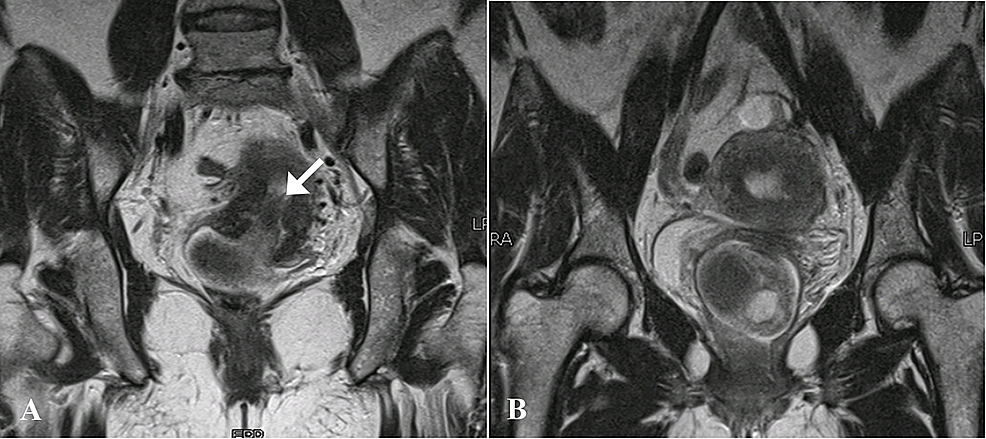

Magnetic resonance imaging (MRI) of the pelvis with contrast was then done which demonstrated a large, well-defined abnormal signal intensity polypoidal mass distending the endocervical canal and extending through the external os (external orifice) into the upper one-third of the vagina. It was measuring 46 x 46 x 58 mm in maximum dimensions. It appeared to be connected to the uterine endometrium by a T2-hypointense stalk seen within the endometrial cavity. No evidence of invasion into adjacent structures was seen. The uterine junctional zone was also thickened and ill-defined, which was suggestive of adenomyosis. The lesion contained rounded T1-hyperintense cystic spaces with fluid-fluid level within it, suggestive of hemorrhages. The lesion did not show significant diffusion restriction, and enhanced heterogeneously in the post-contrast study. Post-contrast enhancement was relatively less than that of myometrium (Figures 3-5).

On ultrasound, polypoid adenomyomas can appear as solid, well-circumscribed endometrial masses with cystic areas [2]. On MRI, they are found to be well-defined intracavitary uterine masses and may involve the lower uterine segment, endocervix or uterine corpus. On T1-weighted images they are usually isointense. Signal intensity on T2-weighted images may depend on the size and amount of glands within the tumor. The presence of a visible stalk passing through the cervix and connecting a prolapsed mass back to the uterus is a helpful imaging finding that is often best appreciated at MRI and indicates a prolapsed uterine tumor, as seen in our patient. The stalk connecting an apparent cervical mass to the endometrial cavity, seen on MR imaging, is referred to the broccoli sign [7]. Some of these tumors may also show hemorrhage within the cystic spaces, which appear as hyperintense foci on T1-weighted images and are not suppressed on fat-suppressed T1-weighted imaging [8].